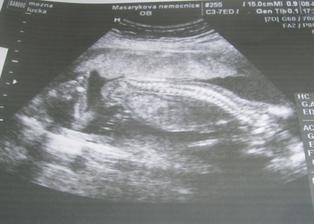

18.září jsme byli na našem 1.IVF... a 8.den od ET se mi "zjevily" nádherné // 🙂... přeju si,aby se všechno vyvíjelo dobře... 29.9 11.den po ET mi pro zhoršení OHSS provedli punkci Douglasova prostoru a odsáli 2 litry žlutého ascitu ☹ Nicméně se mi ulevilo 🙂 HCG ten den 259... 6.10 kontrola HCG - 2950 (18.den od ET)... 10.10 UTZ - čekáme DVOJČÁTKA 🙂 🙂 🙂... 17.10 krvácení a následná hospitalizace, UTZ - dvojčátkům bijí srdíčka, 20.10 HCG - 56000, 25.10 propuštění z nemocnice... 31.10 poslední kontrola v CARu, dvojčátka mají 2 a 2,1 cm... 11.11 UTZ - dvojčátka mají 3 cm... 24.11 UTZ - dvojčátka mají 9 cm (ale moc se mi to měření nezdá, ve čtvrtek na screeningu se ukáže pravda, čeká nás 3D 🙂) 27.11 screening I.trimestru - miminka jsou zdravá, od hlavičky po prdelku mají 7 cm... 19.12 3D - miminko "A" je chlapeček, "béčko" chce zůstat zatím v utajení 🙂 tak snad příště 🙂... 8.1 3D - miminko "B" je holčička 🙂 19.1 echokardiografie - obě srdíčka jsou zdravá 🙂 20.1 screening II.trimestru - vše OK, miminka mají 360 a 364 gramů 🙂 26.1 UTZ - chlapečkovi se ztratil pindík a najednou čekáme 2 holčičky 🙂) Doufám, že už je to definitivní 🙂) 19.2 UTZ 3D4 - holčičky potvrzeny!!! 🙂 mají každá téměř 800 gramů! 🙂 20.3 UTZ - holčičky mají 1700 a 1800 gramů! 8.4 UTZ - holky mají neuvěřitelné váhy 2415 a 2600 gramů! 11.5 nástup do nemocnice... 11.května ve 20,03 se nám akutním císařským řezem narodila Eliška (2970/48) a o minutu později Nelinka (3200/50).Jsme nejšťastnější rodiče na světě! 🙂